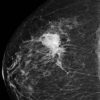

Ung thư vú

» Thông tin: Nữ giới – 55 tuổi.

» Lâm sàng: Khối tuyến vú.